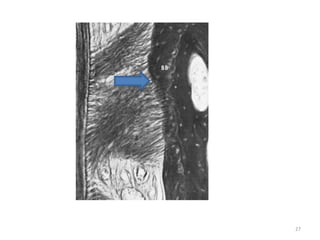

• Radiographic appearance- 0.4 to 0.5 mm space,a

radiolucent area between the radioopaque lamina dura of

alveolar bone proper and radiopaque cementum.